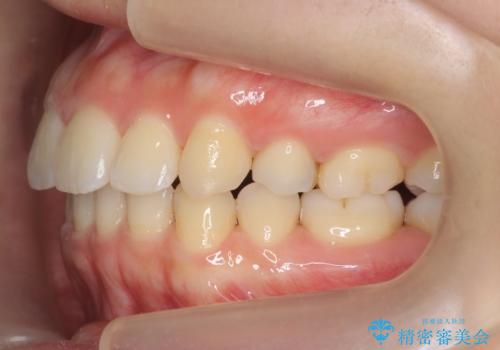

再矯正 昔ワイヤーで治療 前歯の並びを再度きれいに

- 小さいころに小臼歯を抜歯しワイヤー矯正をしたが、すき間が空いてきて、前歯の並びが戻ってしまったとのこと。

インビザラインライトという部分矯正コースで、全体矯正に比べ、比較的安価に治療しました。

前歯の並びが格段にきれいになり、大変喜んでいただけました。